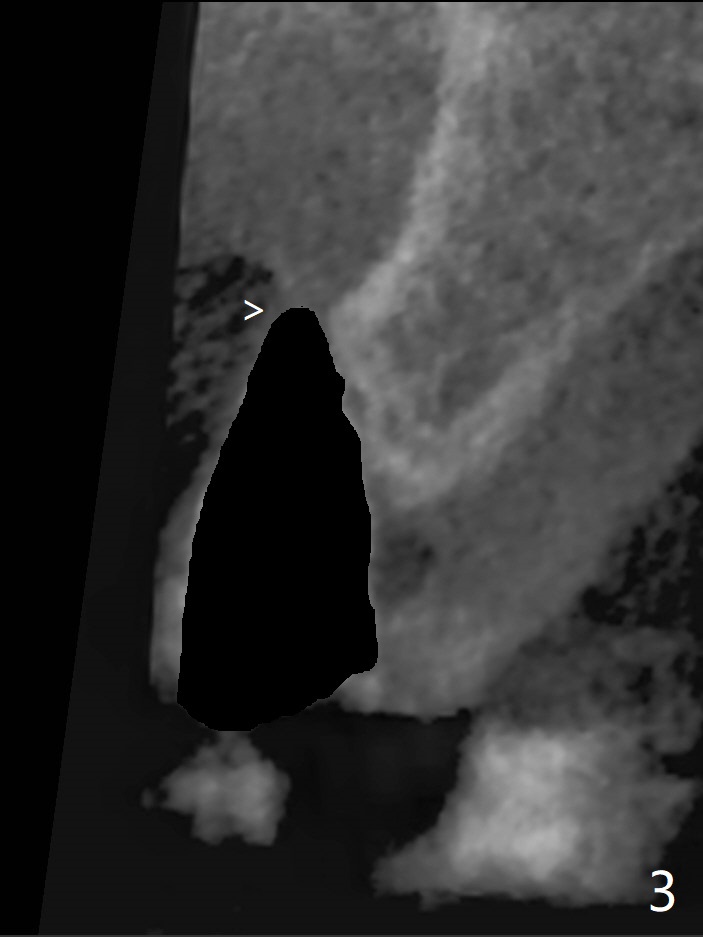

左上尖牙拔除前发现远中腭侧瘘道,拔除后发现相对牙槽嵴骨缺损(图一(术前CT):*),其实患牙根尖在颊侧骨板颊侧(图二:>),拔除后,根尖骨板缺损(图三:>),由于后者离颊侧牙槽嵴(图四:红箭头)远,骨粉修复重要性不如腭侧牙槽嵴(图四:白箭头),当窄植体植入后(图四:绿色),首先在腭侧植骨(图五:红圆圈),因为基台放置后(图六:粉红色),腭侧植骨开口狭窄(图六:白箭头)。即刻种植总是腭侧,颊侧间隙大,颊侧根尖缺损填骨应该容易(图七:橘黄色圆圈),即使不全(*),无关大局。徒手初步钻洞(图八),种植(图九)方向尚可,植骨好像完全(图十:*)。术后一周临时牙冠(11,尖牙)比侧切牙还短(图十一),随着愈合,尖牙牙冠会比双尖牙还短,因为植体偏腭侧,可能需要调整临时牙冠边缘。颊侧牙龈单纯疱疹感染,颊侧根尖仍有疼痛,腭侧瘘道缩小。